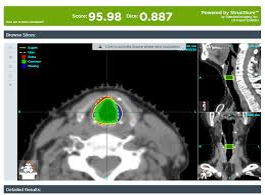

ProKnow提供了一些工具,可以根据患者个人和患者群体的需求,在评分卡中定制临床指标和目标。评分卡有助于推动标准化、提高质量、消除不需要的变动,并证明报销的合理性。

该平台还支持有效性对比,帮助您基于数据,来制定决策,选择最适合您的技术、模式和协议。该解决方案支持所有计划系统和治疗模式,包括IMRT、VMAT、传统的3D外照射、质子、机器人、螺旋弧和近距离放疗。